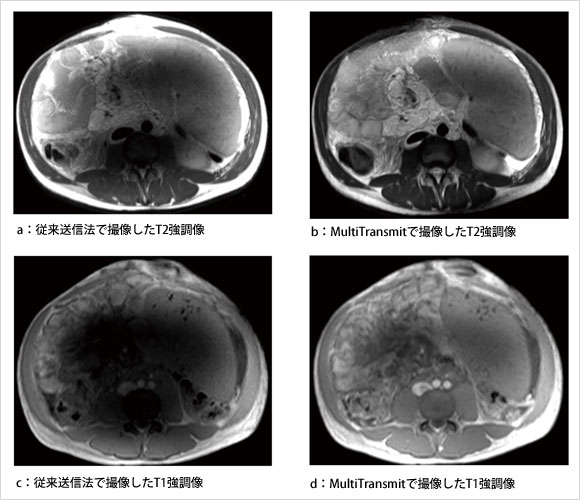

図2は,MultiTransmitで撮像された15名の乳腺のボランティア画像(左:3D T1W,右:脂肪抑制併用3D T1W)の3列表示である。大きさや形状が異なる場合でも,均一な信号強度や脂肪抑制効果が確保されていることがわかる。図3には,腹水および脾臓に拡張を認める患者を従来送信法で撮像した画像(図3 a,c)およびMultiTransmitで撮像した画像(図3 b,d),図4では胎児を従来送信法で撮像した画像(図4 a)とMultiTransmitで撮像した画像(図4 b)を比較している。MultiTransmitにより,従来,信号不均一の影響で困難であった検査も可能となることがわかる。

図3 腹水および脾臓に拡張を認めたケース

(画像ご提供:東海大学病院様)